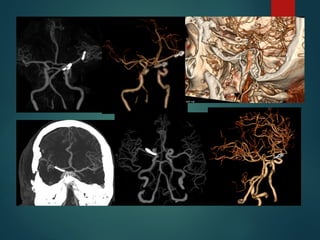

Malformaciones Vasculares

 Las MAV son aglomeraciones anormales focales de arterias y

venas dilatadas en el parénquima cerebral.

 Pérdida de organización vascular a nivel subarteriolar y la

falta de un lecho capilar resulta en un shunt arteriovenoso.

 El nido, está conectado por una o varias fístulas.

Friedlander, et al. N Engl J Med 2007;356:2704-12.

Trombosis Venosa

 Representa un 0.5%.

 Seno Longitudinal Superior y Trasverso.

 ANGIORM mayor sensibilidad respecto del ANGIOTC…